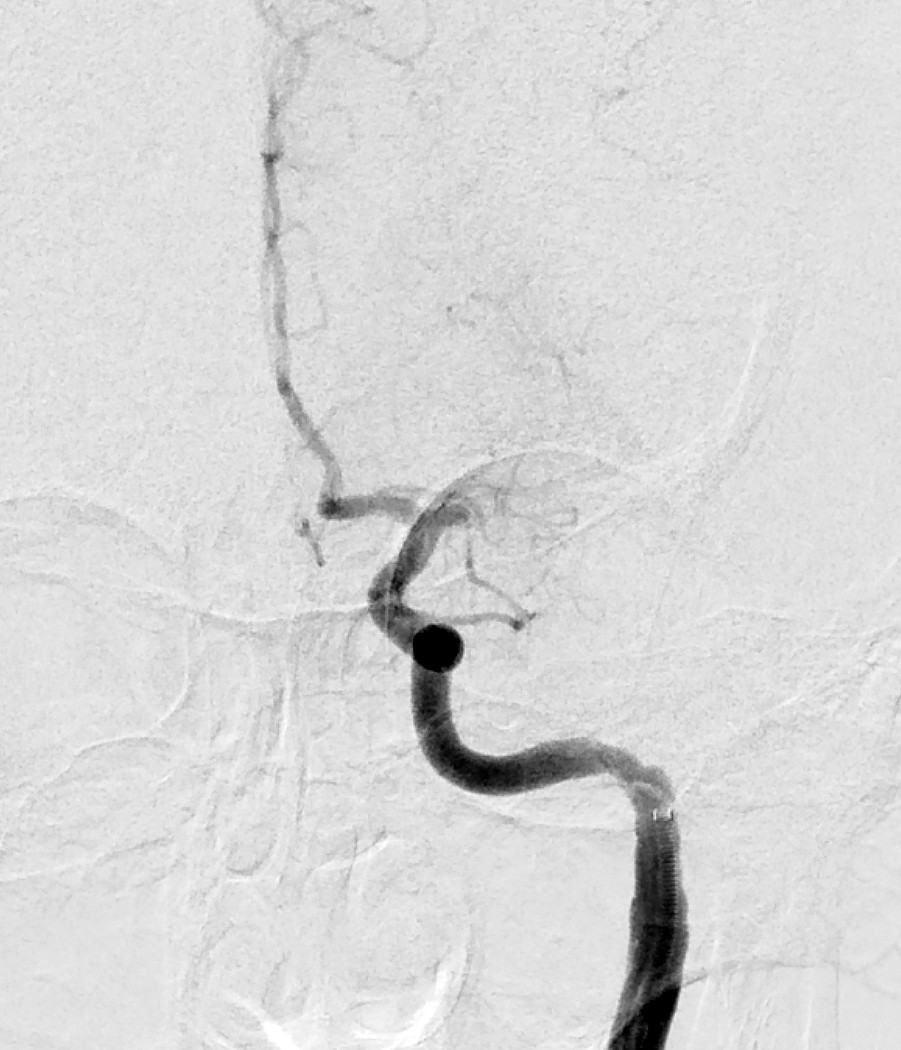

Myren-Svelstad S, Hammer TA, Idicula TT. Early thrombectomy of a proximal middle cerebral artery occlusion leading to complete recovery with no infarct. Case Rep Neurol 2017; 9: 76 - 80. [PubMed][CrossRef]

Vi vil takke for en fin kasuistikk som til fulle viser hvilket potensiale mekanisk rekanalisering (trombektomi) har ved cerebral storarterieokklusjon. Antall som må behandles for én pasient skal komme gjennom et hjerneinfarkt med mindre grad av funksjonshemming (Number Needed to Treat, NNT), er 2,6. I Norge gjennomføres trombektomi per dags dato ved fem sykehus, og to nye sykehus skal starte med trombektomi fra neste år.

De fem store randomiserte trombektomi-studiene inkluderte hovedsakelig pasienter med større nevrologiske utfall. De fleste studiene hadde NIHSS-skår på minst 6 som nedre grense mens MR CLEAN-studien inkluderte pasienter med NIHSS-skår på minst 2 (1). Etter publiseringen av disse studiene er det blitt rutine å trombektomere pasienter også med lettere utfall. I metaanalysene hadde 581 pasienter NIHSS-skår < 8 og 413 pasienter NIHSS-skår ≤ 5. De som ble behandlet med trombektomi, hadde signifikant bedre funksjonsnivå etter 3 måneder sammenliknet med dem som kun fikk medisinsk behandling (2, 3).

Ved St. Olavs Hospital synes man å ha en meget konservativ utvelgelse av pasienter for trombektomi. Forfatterne skriver at behandlingen vanligvis ikke gjøres ved NIHSS-skår < 10. Vi mener i overenstemmelse med publiserte metaanalyser at en slik høy grense for intervensjon gjør at endel pasienter går glipp av svært viktig akuttbehandling. Målet med trombektomi er å begrense skadevolumet i hjernen, ikke å reperfundere et hjernevolum som allerede er nekrotisk. Ved de andre trombektomi-sentrene i Norge vektlegges derfor CT/MR penumbra-vurdering, kollateralsirkulasjon og eventuelt diffusjonsfunn på MR sterkere enn selve NIHSS-skåren når indikasjonen for trombektomi stilles. I OUS-materialet fra 2017 hadde 39 av totalt 120 pasienter (32,5 %) NIHSS-skår < 10 på indikasjonstidspunktet (abstrakt presentert på Nevrodagene 2018 ved B. Enriques og medforfattere). Disse hadde klinisk og radiologisk et stort truet penumbravolum. Ved å bruke høy NIHSS-skår som indikasjon og ikke en individuell fysiologisk tilnærming vil trolig for få pasienter bli behandlet og det samlete resultatet etter trombektomi bli vesentlig dårligere enn det kunne ha vært.

Vi takker Anne Hege Aamodt og medarbeidere for en hyggelig og viktig kommentar. Beklageligvis ligger pasientkasuistikken noe tilbake i tid, utarbeidelse av manuskript likeså. I Trondheim benyttes CT/MR for vurdering av penumbra og kollateralsirkulasjonen vektlegges. At NIHSS-skår ikke kan benyttes som indikasjon alene er selvsagt, og denne misforståelsen beklager vi. Samtidig bør det være et visst nevrologisk utfall før en invasiv prosedyre utføres. Ved St. Olavs hospital gjøres i dag normalt ikke trombektomi ved NIHSS-skår ≤ 5, men alle pasienter som kan være kandidat til trombektomi, får en individuell vurdering, også de med lavere NIHSS-skår.